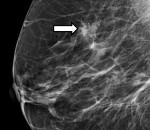

• Маммография. Основной целью исследования является получение предварительных выводов о происхождении кальцинатов. На рентгеновском снимке отложения обычно имеют одинаковые размеры, структуру, четкие контуры и форму, характерную для дольковых и стромальных образований. Подозрительными в плане злокачественного процесса считаются множественные микрокальцинаты и образования с расплывчатыми границами, напоминающие кусочки ваты.